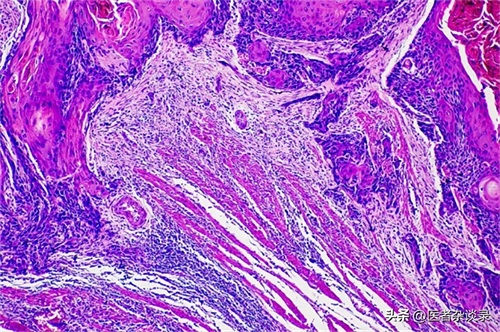

结合赵先生的长期嚼槟榔史,医生怀疑赵先生可能患上了口腔癌,建议他进行口腔活检以确定诊断。

赵先生进行了口腔活检,发现活检组织中存在癌症细胞。

长期咀嚼槟榔后,槟榔中的槟榔碱、多酚和亚硝胺等物质可能会破坏口腔内部的微生态平衡,使发生氧化应激反应,损伤细胞从而激发炎性因子,促使上皮细胞在短时间内凋亡,同时还会阻止机体清除细胞外基质的蛋白质,导致蛋白沉积,进而造成口腔黏膜下纤维化(OSF)。患有OSF的患者通常会有口腔上皮萎缩、黏膜逐渐变硬、溃疡、张口受限等问题,且有可能会发展形成口腔癌。

另外,人们在食用槟榔时,口腔和胃部的细菌会产生一氧化氮,在一氧化氮环境下,这些生物碱会进行亚硝化反应,产生大量亚硝胺代谢物,增加细胞毒性和基因毒性;而亚硝胺与细胞其他分子相互作用后可能会加速口腔癌前病变,从而导致癌症的发生。